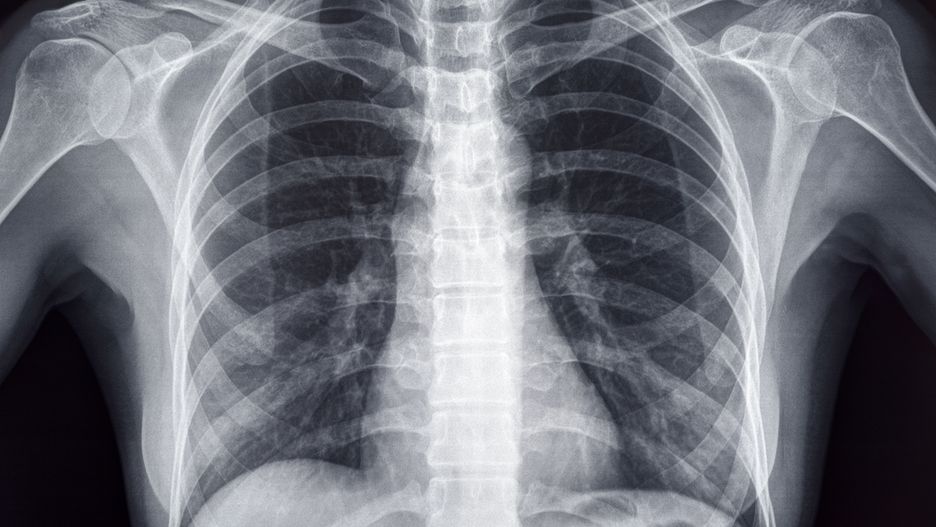

Złamanie mostka - objawy, diagnoza, leczenie

Złamanie mostka następuje głównie w wypadkach komunikacyjnych, gdy klatka piersiowa uderza o kierownicę lub w wyniku zmiażdżenia. Od kiedy jazda samochodem z zapiętymi pasami bezpieczeństwa stała się obowiązkowa, notuje się więcej przypadków tego typu urazów. Najczęściej złamaniu ulega trzon mostka, rzadko z przemieszczeniem. Jest to uraz ciężki, który może powodować uszkodzenie narządów wewnętrznych klatki piersiowej, w szczególności serca i płuc.

Złamanie mostka rozpoznaje się na podstawie zdjęcia rentgenowskiego. Niekiedy konieczna jest również tomografia komputerowa. Chorzy powinni zostać na obserwacji w szpitalu – należy bowiem upewnić się, czy nie doszło do stłuczenia serca. Złamania mostka z przemieszczeniem do śródpiersia kwalifikują się do leczenia operacyjnego, nastawienia złamania i zespolenia odłamów.